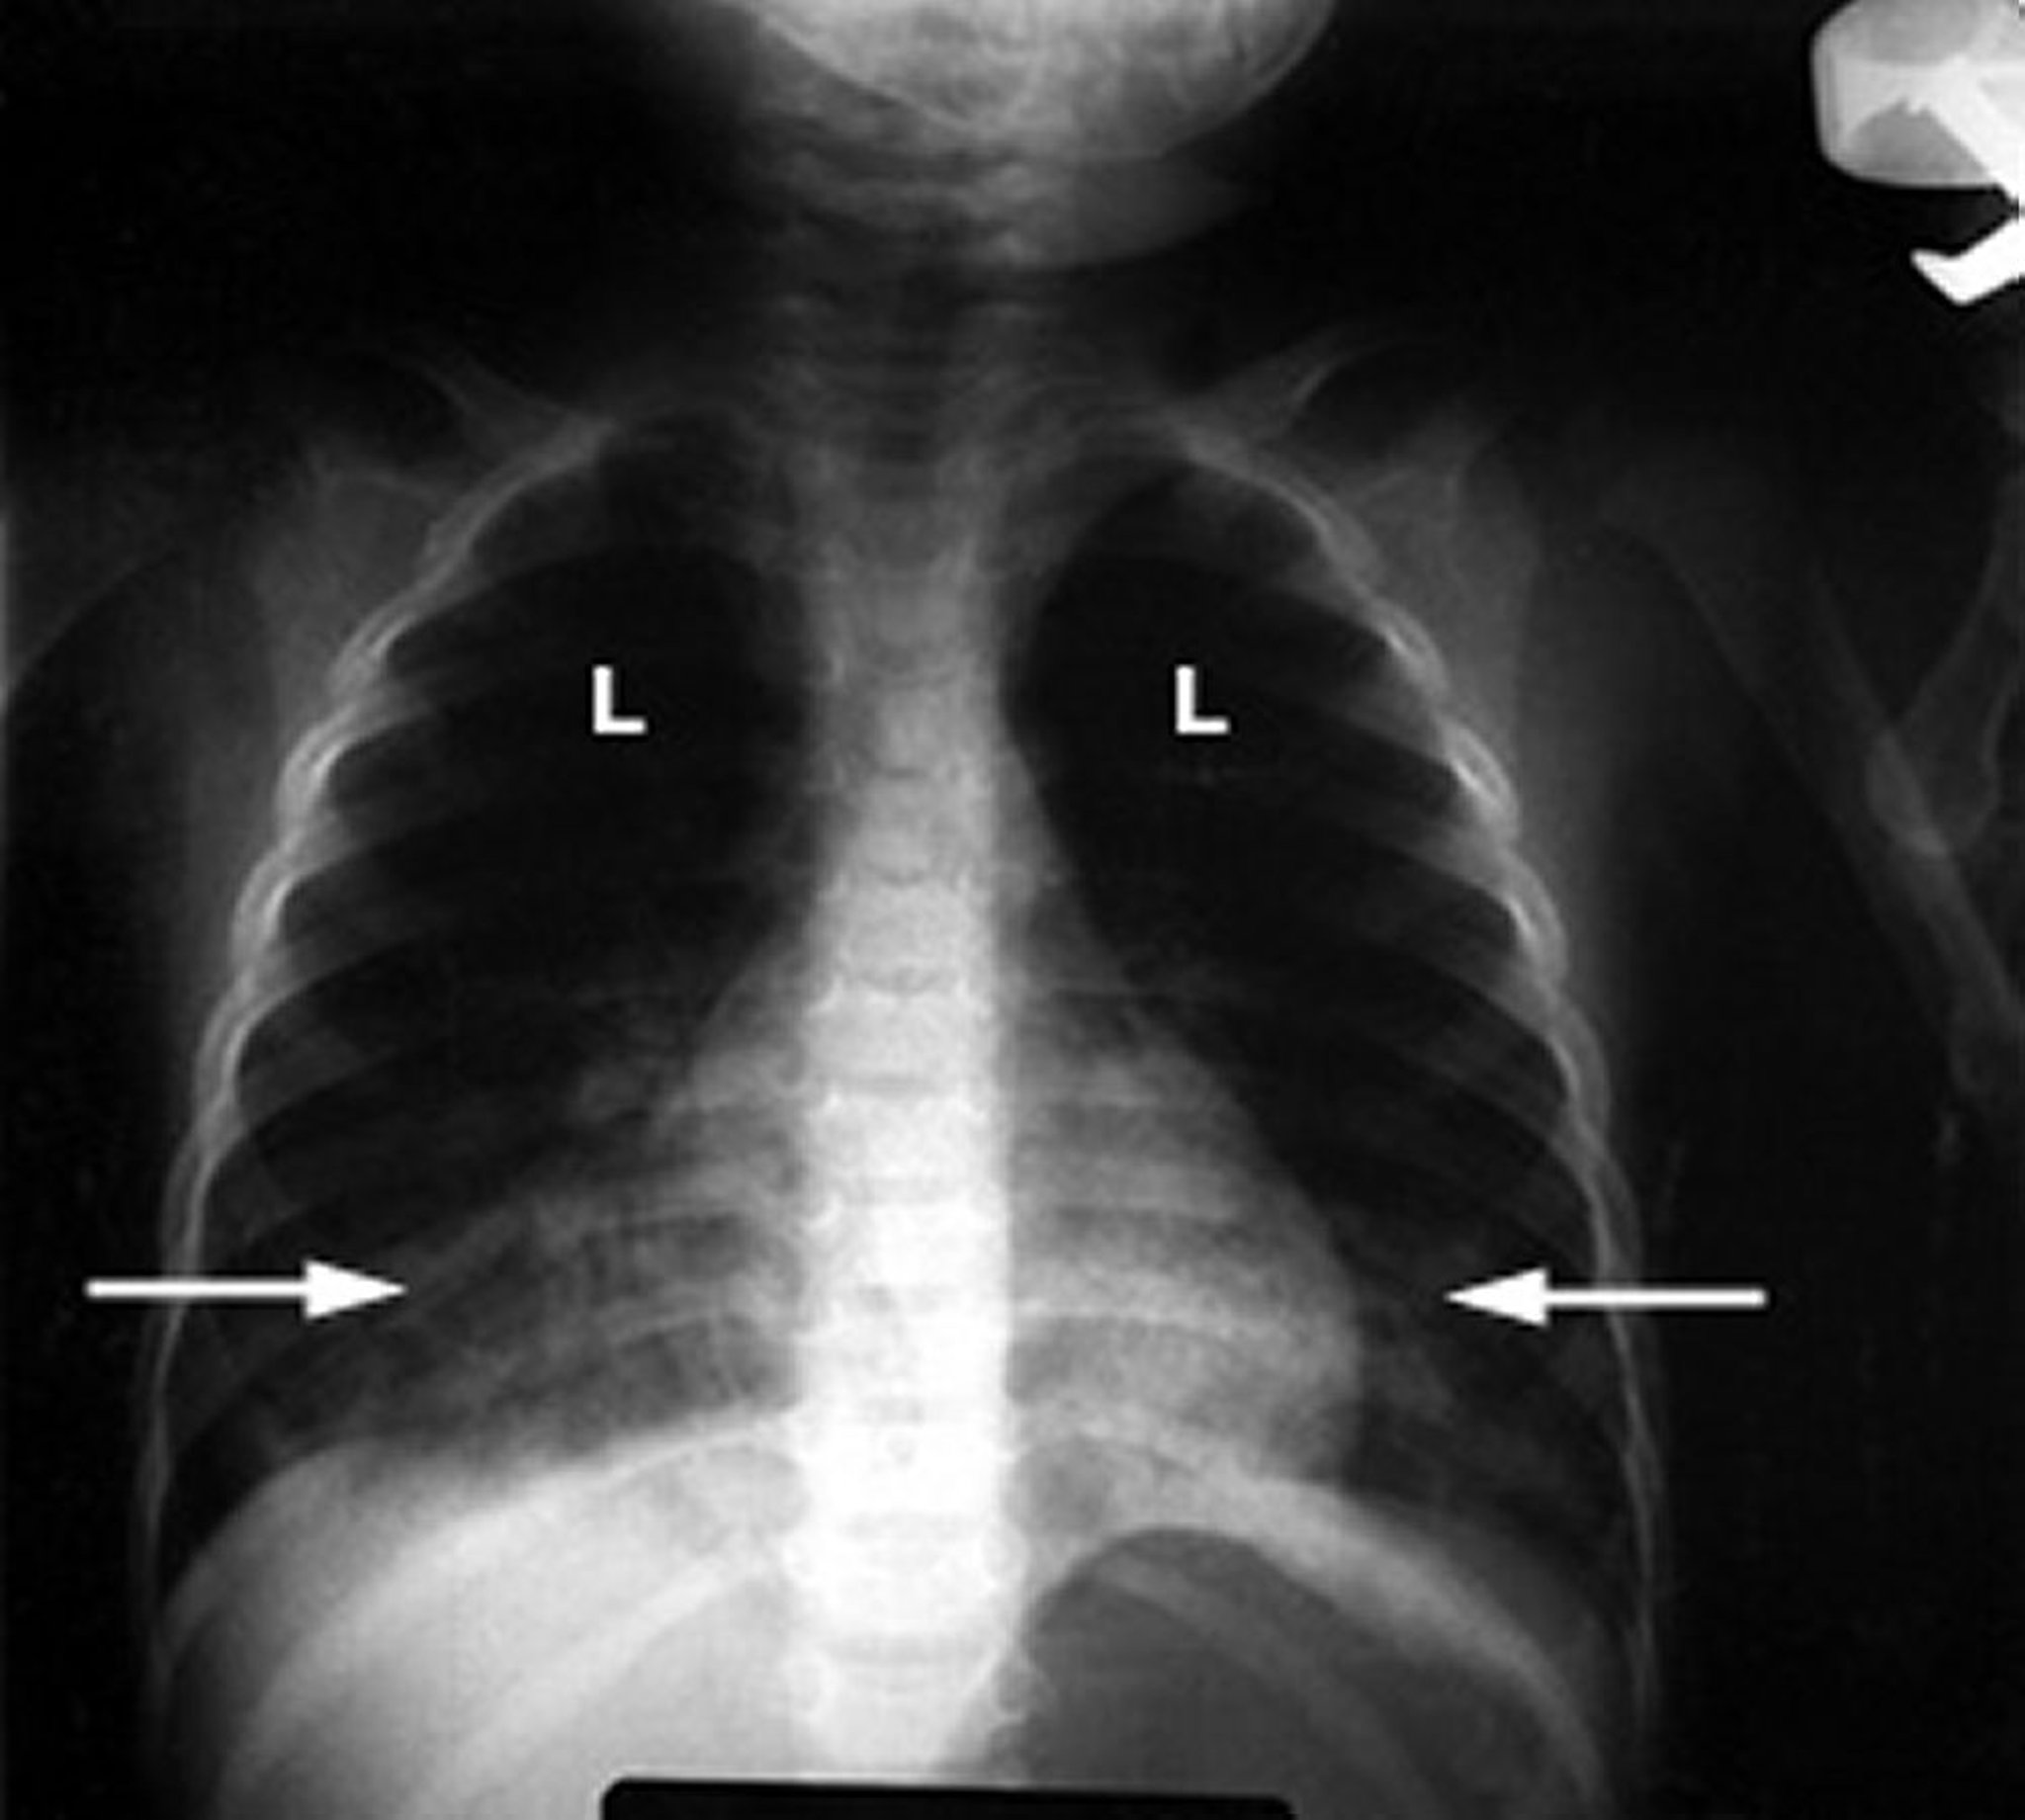

Uma radiografia do tórax anormal em um bebê mostra infiltrados brancos esponjosos (setas) nos pulmões (L), indicando inflamação. Esse resultado é típico de lesão pulmonar devido a intoxicação por hidrocarbonetos.

Cortesia do Dr. G. Schmidt.